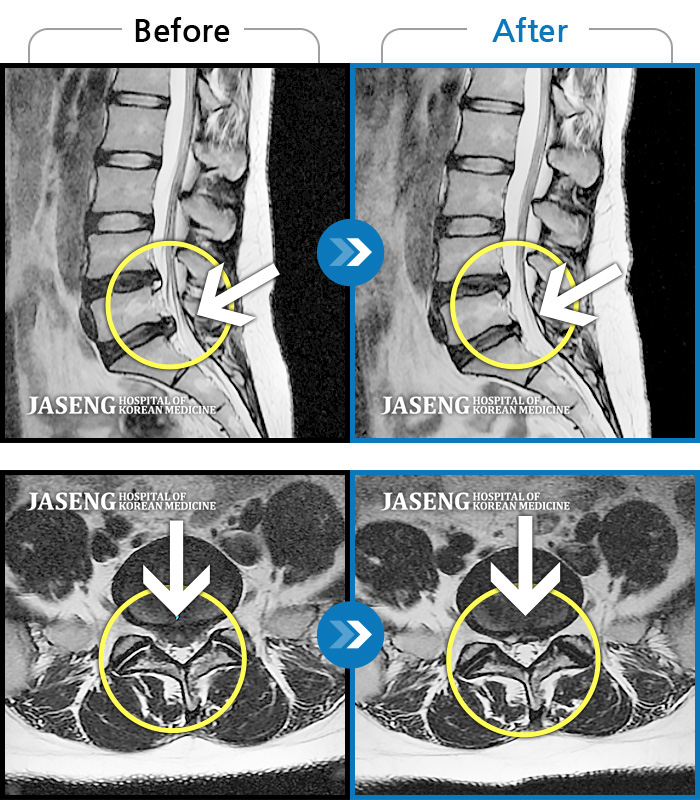

허리디스크

보라매 · 왕오호 원장

허리와 좌측 엉치 통증

촬영시기

2015.12.29 ~ 2018.10.11

2018.12.28

조회수 3,338